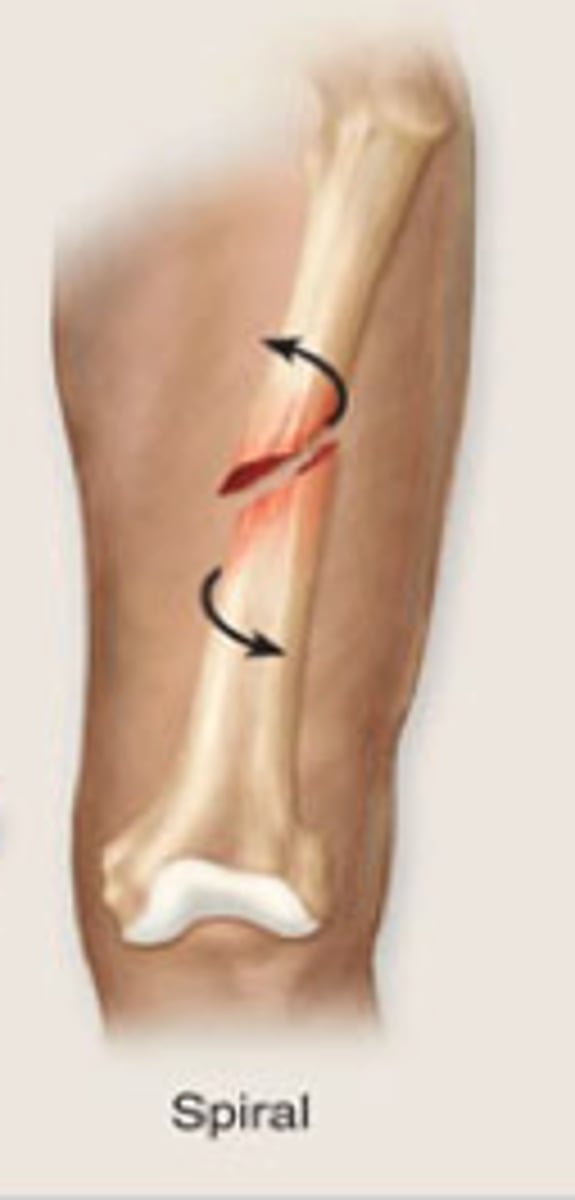

Spiral fracture

a fracture in which the bone has been twisted apart